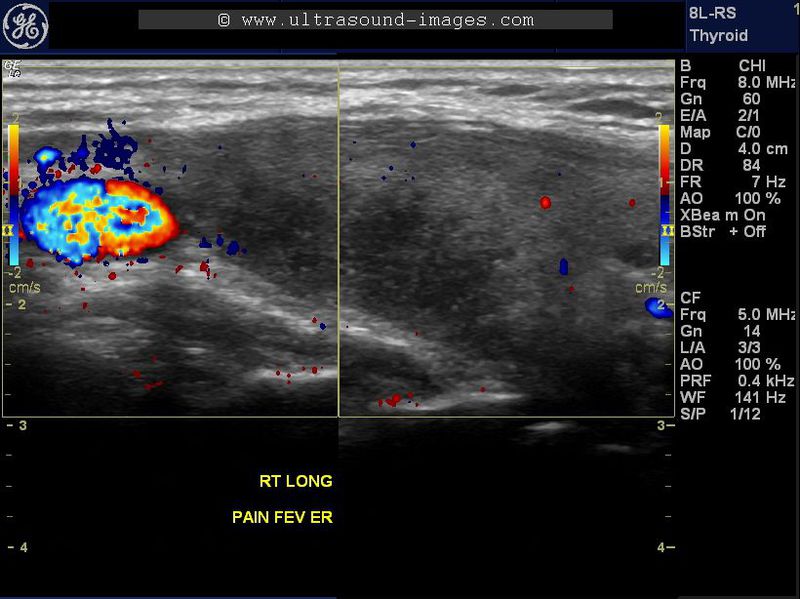

De-Quervains-thyroiditis-or-subacute-thyroiditis

This elderly female patient presented with pain in the neck and intermittent fever. Ultrasound imaging of the thyroid gland shows markedly hypoechoic lesions in the right lobe. Color and Power Doppler ultrasound failed to show significant vascularity within the affected area (lesion) in the right lobe. The hypoechoic thyroid lesion shows irregular borders and is seen to infiltrate along the long axis of the affected lobe. Follow up ultrasound images show that the lesion has increased in size and also shows patchy involvement of the left lobe also. Again there is no vascularity in the affected hypoechoic lesions and marked tenderness is presented in these lesions on probe pressure. These sonographic findings are suggestive of De Quervain's thyroiditis, also known as subacute thyroiditis.